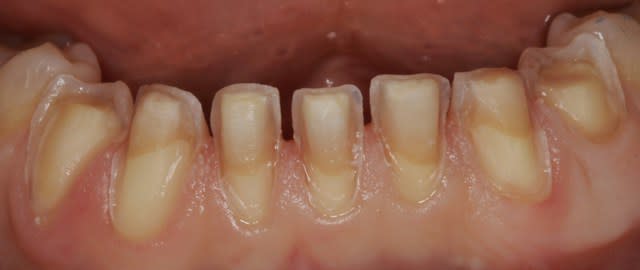

Tient, un petit cas de facettes sur les incisives du bas pour changer du haut...cas de décoloration, résistant au blanchiment...c'était pas mon apn...je testais un Canon 50D, 100mm canon, flash Mr-14X...pas mal.

Bof, les tailles sont moches, ça va pas coller, besoin de 5 ou 6 endo, puis des implants...